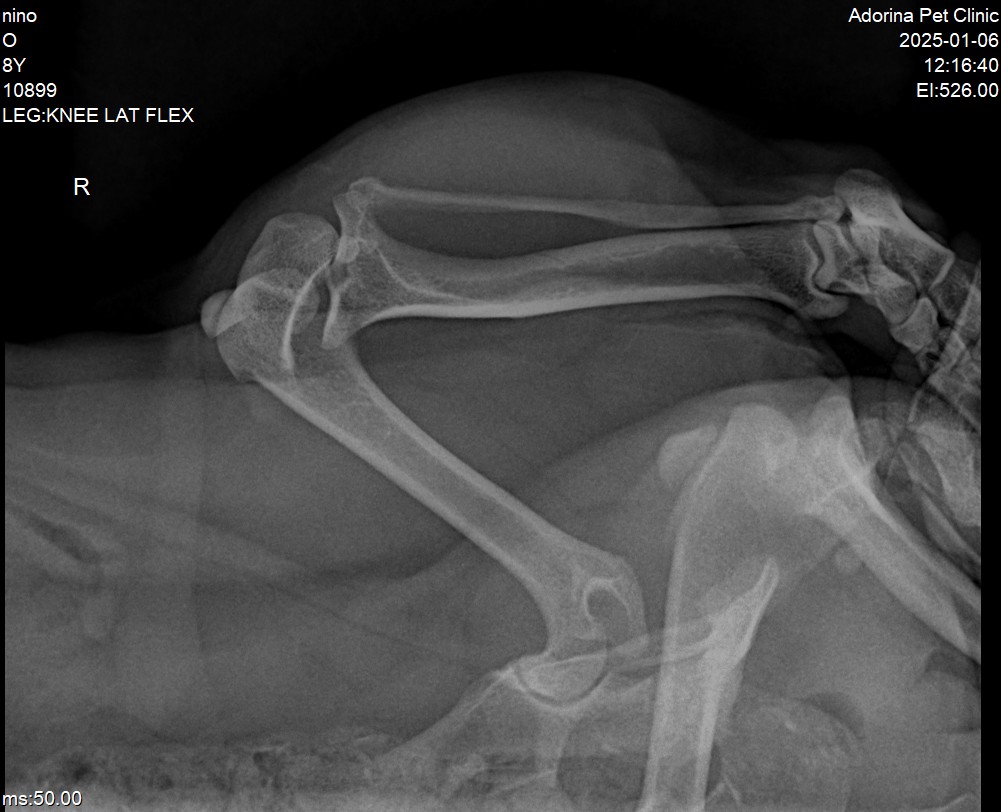

رادیوگرافی  یا تصویر برداری با اشعه ایکس یکی از ابزارهای حیاتی در تشخیص دررفتگی  کشکک (Patellar Luxation) در سگ‌ها است. این روش تصویربرداری می‌تواند  اطلاعات ارزشمندی در مورد وضعیت ساختاری و موقعیت استخوان‌ها و مفاصل زانو   ارائه دهد. در ادامه به نقش و کاربرد رادیوگرافی در تشخیص این عارضه اشاره   شده است:

1. تأیید تشخیص

• مشاهده  موقعیت کشکک: رادیوگرافی به دامپزشک اجازه می‌دهد تا به طور مستقیم موقعیت  کشکک را مشاهده کند و تأیید کند که آیا کشکک از شیار خود خارج شده است یا  خیر. این مسئله برای تأیید دررفتگی و  درجه آن بسیار مهم است.

2. تعیین درجه دررفتگی

• تشخیص  شدت دررفتگی: با کمک رادیوگرافی، دامپزشک  می‌تواند تعیین کند که دررفتگی  کشکک تا چه اندازه شدید است. اگر کشکک به طور مداوم در خارج از شیار قرار  دارد، احتمالاً مشکل جدی‌تری وجود دارد که نیاز به مداخلات گسترده‌تر دارد.

3. ارزیابی تغییرات استخوانی و مفصلی

• بررسی  ناهنجاری‌های ساختاری: رادیوگرافی می‌تواند  ناهنجاری‌های ساختاری در  استخوان‌ها و مفاصل، مانند تغییرات در زاویه عناصر  استخوانی، اپی‌فیزها یا  مکانیزم‌های پشتیبان را نشان دهد.

• وجود  تغییرات استئوآرتریتیک: در مواردی که دررفتگی به مدت طولانی وجود داشته  باشد، رادیوگرافی ممکن است علائم تغییرات التهابی یا استئوآرتریتیک را نشان  دهد که می‌تواند بر تصمیم‌گیری درمانی تأثیر بگذارد.

4. ارزیابی ناهنجاری‌های همراه

• تشخیص  مشکلات دیگر در مفصل زانو: علاوه بر دررفتگی کشکک، رادیوگرافی می‌تواند به  شناسایی یا رد مشکلات مرتبط دیگری مانند شکستگی یا ناهنجاری در دیگر اجزای  مفصل زانو کمک کند.

5. برنامه‌ریزی جراحی

• برنامه‌ریزی  پیش از مداخله جراحی: در مواردی که نیاز به جراحی برای اصلاح دررفتگی کشکک  وجود دارد، رادیوگرافی اطلاعات دقیقی در خصوص وضعیت فعلی استخوان‌ها و  مفاصل ارائه می‌دهد که کمک می‌کند  برنامه‌ریزی دقیق‌تری برای جراحی انجام  شود.

6. پیگیری درمان

• ارزیابی  موفقیت مداخلات درمانی: پس از انجام مداخلات درمانی، رادیوگرافی می‌تواند  به عنوان یک ابزار پیگیری برای ارزیابی موفقیت درمان و اطمینان از تثبیت  کشکک در محل صحیح به‌کار رود.